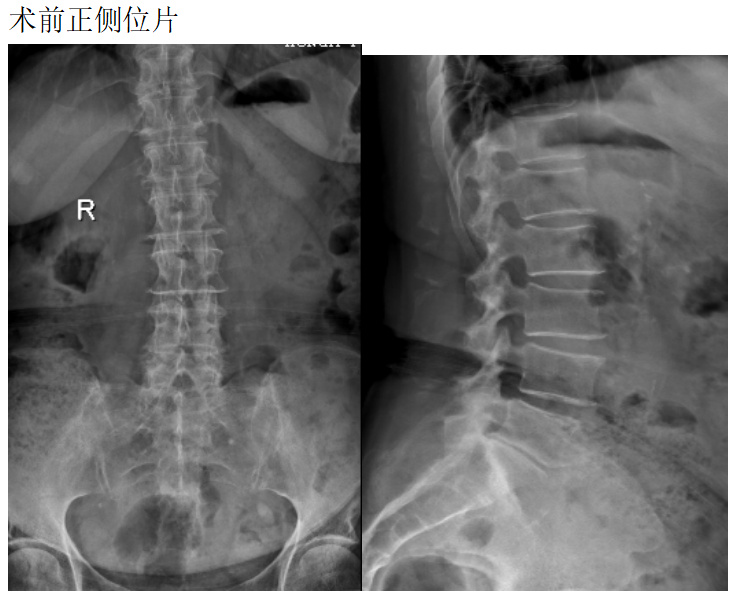

患者女性78岁,主诉:双下肢酸困麻木1年

现病史:1年前出现双下肢酸困麻木,以右侧为主,行走及站立时症状加重,平卧休息稍减轻,未治疗,上述症状持续加重,步行困难,步行能力约100米,为求诊治,现来我院,遂以“腰椎管狭窄症”为诊断收住我科。发病以来,饮食正常,睡眠一般,体力正常,大小便正常。